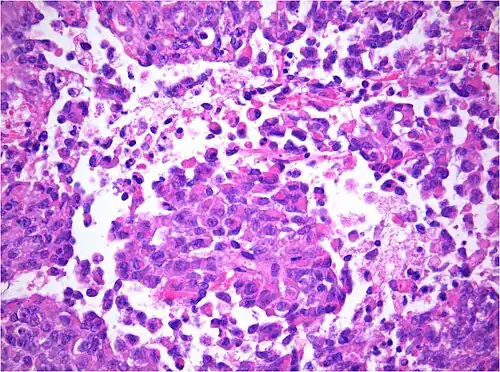

AT/RT and rhabdoid tumor share the term "rhabdoid" because under a microscope, both tumors resemble rhabdomyosarcoma.

Histology

The tumor histopathology is jumbled small and large cells. The tissue of this tumor contains many different types of cells including the rhabdoid cells, large spindled cells, epithelial and mesenchymal cells, and areas resembling primitive neuroectodermal tumor (PNET). As much as 70% of the tumor may be made up of PNET-like cells. Ultrastructure characteristic whorls of intermediate filaments are seen in the rhabdoid tumors (as with rhabdoid tumors in any area of the body). Ho and associates found sickle-shaped embracing cells, previously unreported, in all of 11 cases of AT/RT.[24]

Immunohistochemistry

Immunohistochemistry for INI1, the product of the SMARCB1 gene typically defective in AT/RT: Note the loss of brown staining in the nuclei of tumor cells with defective SMARCB1 as compared to retained staining of nuclei of vascular cells (internal positive control).

Immunohistochemical staining is widely used in the diagnosis and treatment of cancer. Specific molecular markers are characteristic of particular cancer types. Immunohistochemistry is also widely used in basic research to understand the distribution and localization of biomarkers in different parts of a tissue. Proteins found in an ATeratoid/RT are: